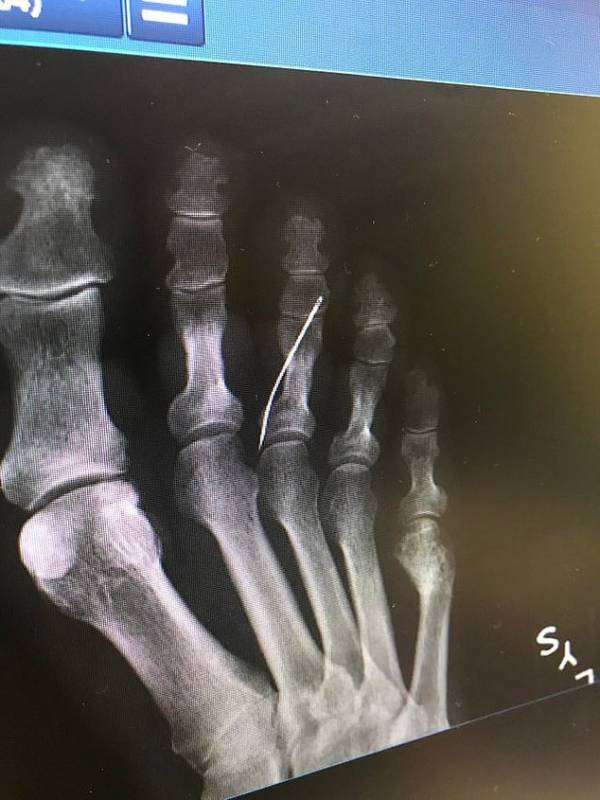

مادربزرگی که نامش منتشر نشده است هنگام عبور از اشعه ایکس متوجه واقعیتی شد که باور کردنی نبود او سوزن خیاطی در پایش داشت که هیچ توجیهی برای آن نداشت .خرید رپورتاژ آگهی

تصویر قابل توجهی که در این بخش از سرگرمی نمناک مشاهده می کنید در فضای مجازی به اشتراک گذاشته شد، با یادداشتی که نشان می داد این زنی که نامش ذکر نشده است، به دلیل مرض دیابت حس را در پایش از دست داده است و از وجود سوزنی که در پایش بوده هیچ اطلاعی نداشته. نوه ی او که اهل کالیفرنیا بود تصاویر او را به اشتراک گذاشت کاربران زیادی نظرات متفاوتی داشتند اما او وقتی به پزشک مراجعه کرد سریع او را به طور اورژانسی عمل کرده و سوزن را بیرون آوردن عفونت پای او به حدی بود که باید در بیمارستان می ماند و حالا هیچ معلوم نیست چقدر طول بکشد تا پوستش التیام پیدا کند.

سوزنی که به داخل پای پیرزن رفته بود